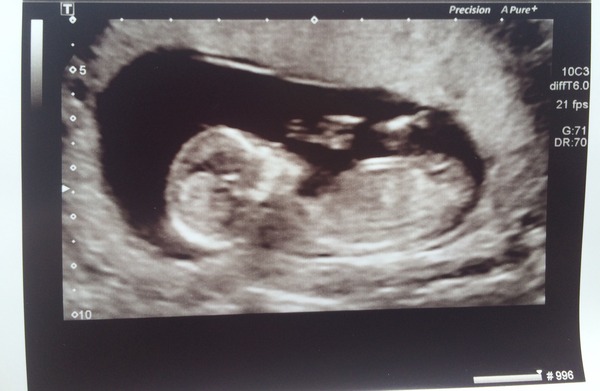

It's a baby!!!! Grin

It was the most amazing feeling ever seeing it on the screen!!! So happy!! It was so clear! Everything was fine and healthy. Now 13+1 due 26th of January xxx

DH sat & stared at the screen - bless. He kept commenting on how wriggly it was!! When she started it stretched right out & we could see its hands & fingers!! Surreal! I was in for 2 hours!! Had drank too much water so had to pee then do star jumps then got sent down for sugar cos she couldn't do the dating or any other measurements lol but they were all lovely & loved the experience. I haven't stopped smiling since. Such a relief!!! I'm thinking boy! We got loadssss of photos - hard to pick one!!

Saw 2.5 NT on the screen but all she said was everything measured fine. Who knows.